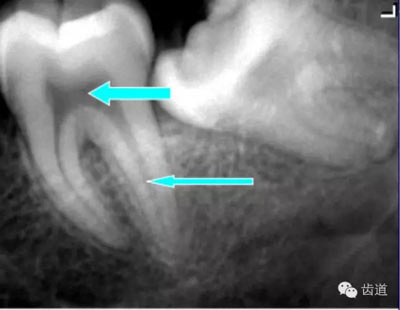

5)下頜管:

位于磨牙牙根尖下方,呈寬約為0.4cm凹面向下邊緣整齊的帶狀密度低的影像,其兩側(cè)有密度高的線條狀影像,為下頜管骨密質(zhì)